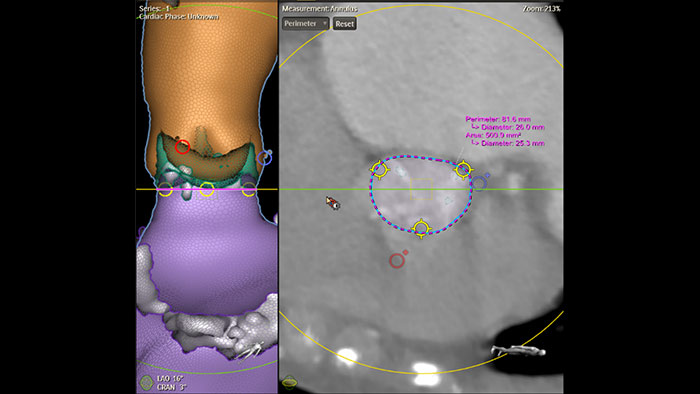

Dimensionamiento de la TAVR totalmente automatizado con HeartNavigator

Evaluación automatizada de la ruta de acceso Intellispace Cardiovascular